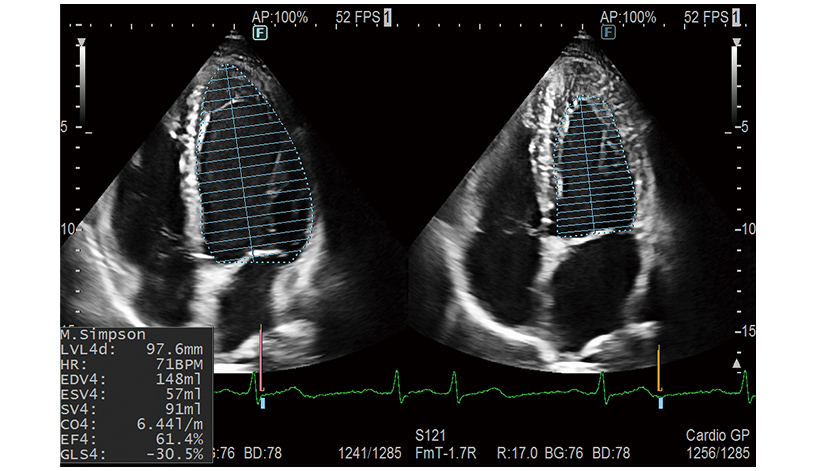

Supports the automated measurements which are effective for cardiovascular examinations using AI technology*1. Users can perform examinations smoothly and efficiently.

- LV, LA, RA Volume auto measurement